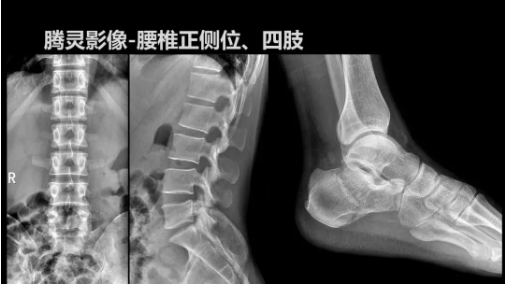

相較前代產(chǎn)品,“騰靈”在圖像質(zhì)量方面得到了全面升級(jí),“騰靈”采用17*17非晶硅平板探測(cè)器設(shè)計(jì),采集矩陣達(dá)3072*3072,動(dòng)態(tài)范圍達(dá)16bit,為成像提供超大視野的同時(shí)保證成像質(zhì)量,此外,該款機(jī)型可根據(jù)醫(yī)療機(jī)構(gòu)的差異化需求而選配不同的動(dòng)態(tài)平板探測(cè)器,以此來適應(yīng)不同階層用戶所需。

此外,“騰靈”為了能夠幫助醫(yī)生更快速、有效的定位病灶,還增加了多項(xiàng)精準(zhǔn)診斷保障功能,如支持動(dòng)態(tài)觀察診斷,實(shí)時(shí)高清點(diǎn)片等?!膀v靈”透視切換高清點(diǎn)片曝光,捕捉關(guān)鍵病灶診斷僅需0.8s,同時(shí)還支持圖像局部放大,醫(yī)生可自由切換15’12’和9’三種放大模式,另外,“騰靈”還支持視頻保存、回放功能,幫助醫(yī)生在檢查結(jié)束后通過回放查看細(xì)節(jié),為醫(yī)生的診斷增加信心。